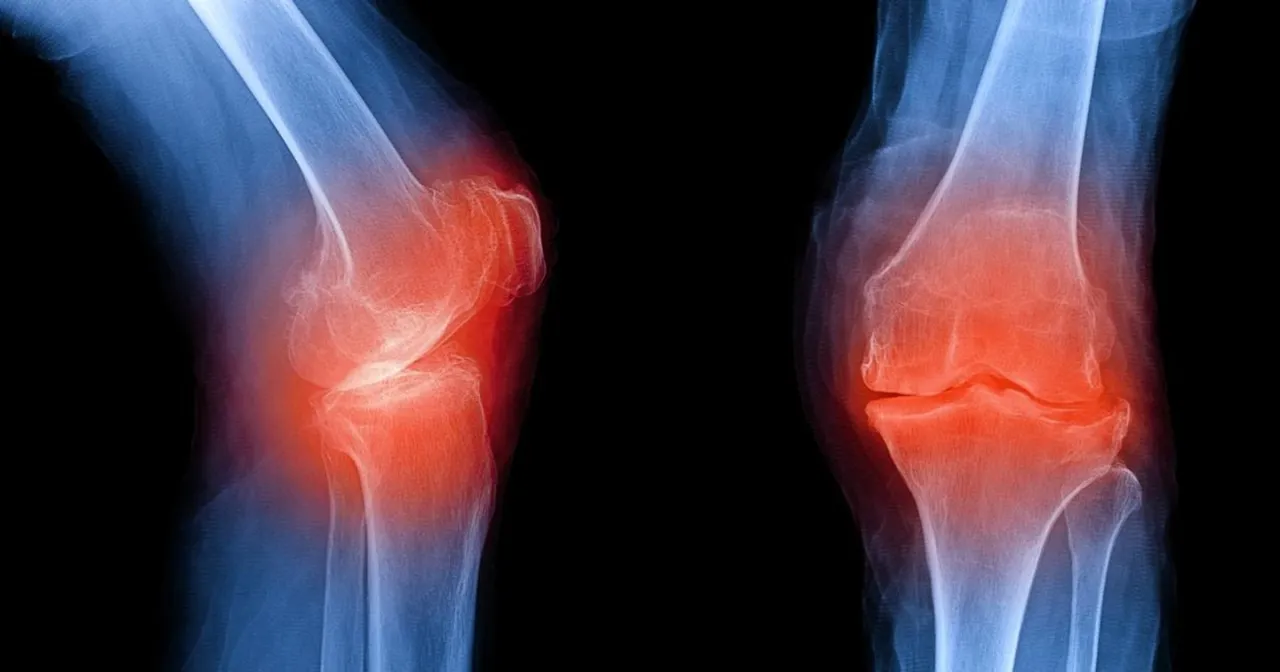

Osteofitoza to schorzenie, które dotyka wiele osób, prowadząc do bólu i ograniczenia ruchomości stawów. Rehabilitacja w przypadku osteofitozy ma na celu łagodzenie bólu, poprawę funkcji stawów oraz zatrzymanie postępu choroby. Ponieważ nie istnieje metoda, która bezpośrednio zmniejsza rozmiary osteofitów, kluczowe jest holistyczne podejście, które łączy różne formy terapii, w tym farmakoterapię, fizjoterapię oraz zmiany stylu życia.

Rehabilitacja w przypadku osteofitozy jest kluczowym elementem w zarządzaniu bólem oraz poprawie funkcji stawów. Jej głównym celem jest łagodzenie objawów oraz spowolnienie postępu choroby, ponieważ obecnie nie ma metod, które mogłyby bezpośrednio zmniejszyć rozmiary osteofitów. Dlatego holistyczne podejście, które łączy różne formy terapii, takie jak farmakoterapia, fizjoterapia oraz zmiany stylu życia, staje się niezbędne.